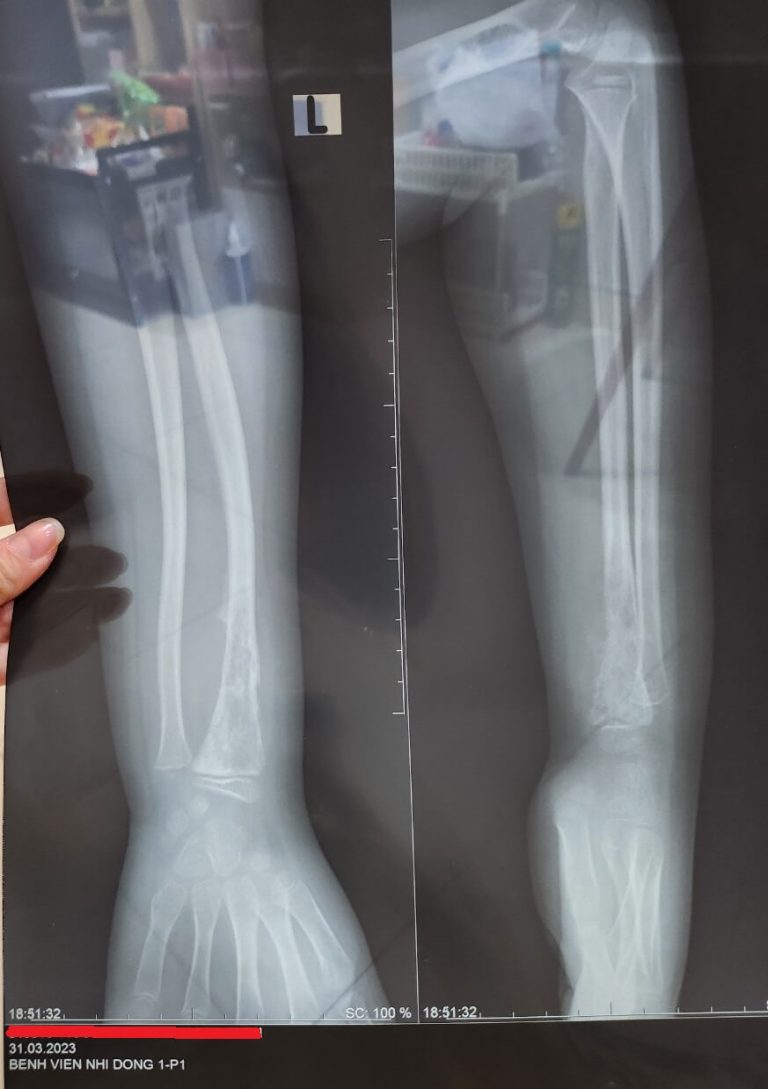

Ngày định mệnh – ngày 0 của Hành trình đối mặt với Ung Thư Xương Sarcoma tại Singapore

Khi bạn tìm đến bài viết này để hiểu về Ung Thư Xương Sarcoma – chắc hẳn gia đình bạn …